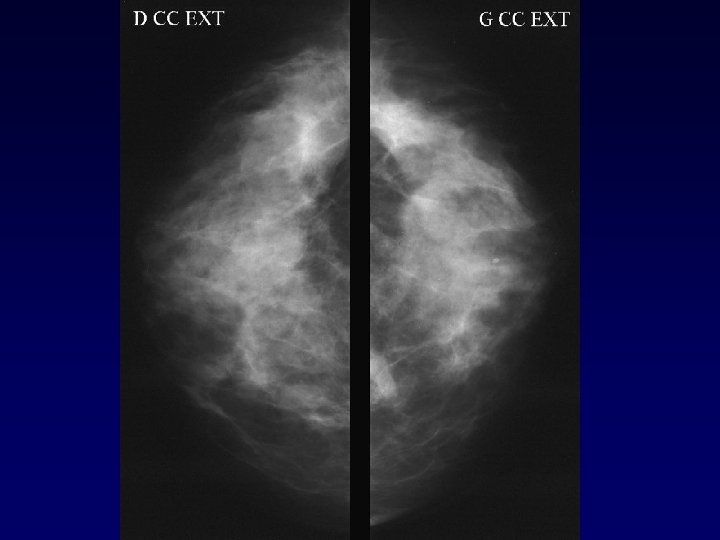

Analyse faux-négatif • • • Corrélation avec analyse de pièces de mastectomies coupées en 5 mm 99 seins (188 K) IRM : Sen = 81 % (89 % KI, 40 % KIS) MM : Sen = 66 % (72 % KI, 37 % KIS) F- : IRM : 5, 6 mm, MM : 10, 9 mm Performance = sein densité BIRAD 1 AJR Sardanelli 2005

Analyse Faux négatif K invasif 28 cas (Teifke adiology 2002) • Technique : 5 cas • Rehaussement masquant : 3 cas • Caractéristiques histologiques : 5 cas • Taille : 15 cas : ≤ 5 mm